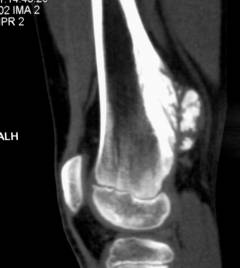

- Компьютерная томография:

- участки некроза внутри опухоли

- живые опухолевые клетки вокруг сосудов

- поражение мягких тканей превышает размеры опухоли

- размягчение связок и сухожилий вблизи опухоли

- очаги поражения костного мозга

- Магнитно-резонансная томография (МРТ) с контрастным веществом гадолиниума позволяет выявить:

- скопление контраста вокруг опухоли, определяющее ее размеры

- наличие метастазов

- разрушение окружающих тканей (костей и кожи)

- разволокнение надкостницы

- утолщение суставных поверхностей костей.